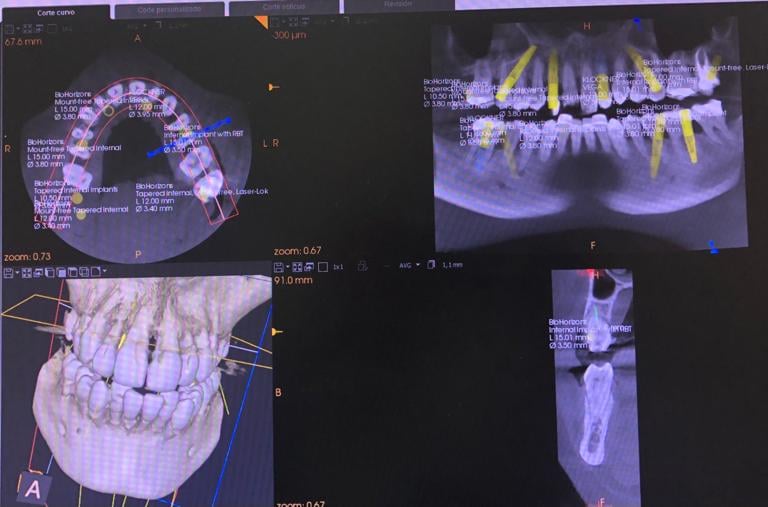

Trabajamos bajo un principio irrenunciable: mínima invasión, máxima precisión. Cada intervención se planifica de forma personalizada, buscando el equilibrio entre salud, función y estética. Combinamos protocolos basados en evidencia con diagnóstico digital, flujos CAD/CAM, guías quirúrgicas y materiales de última generación para obtener resultados naturales y duraderos, evitando procedimientos innecesarios.

NUESTROS CASOS REALES